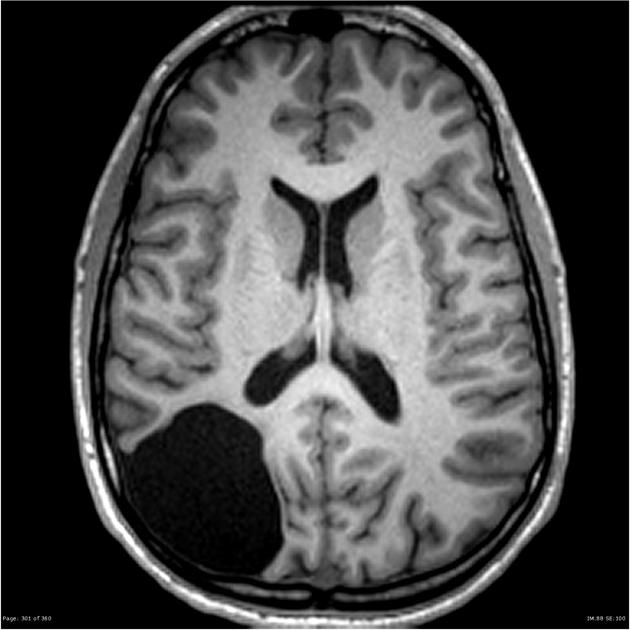

arachnoid cyst

often congenital

extra-axial

same as CSF signal